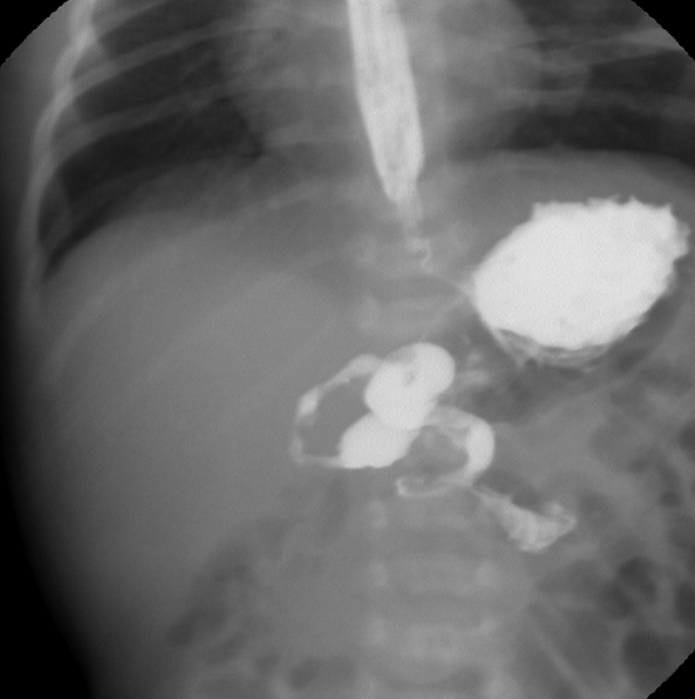

A 52-year-old man is brought to the emergency department after he was hit by a car while crossing the street. Initial trauma workup does not reveal any fractures but shows bruising to the extremities, right chest, and upper abdomen. Eight hours after the accident, the patient develops right-sided chest discomfort and shortness of breath. Blood pressure is 130/80 mm Hg, pulse is 102/min, and respirations are 24/min. Pulse oximetry is 90% on room air. Physical examination shows bronchial breath sounds at the right base and normal S1 and S2 heart sounds. The abdomen is soft and nontender. The patient’s chest x-ray is shown in the image below:

Which of the following is the most likely diagnosis?